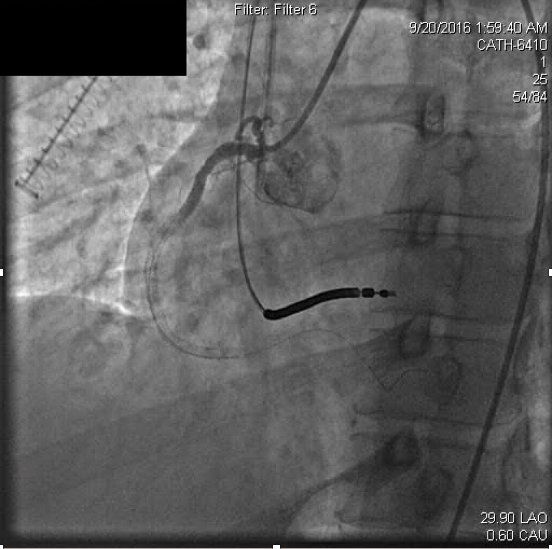

Myocardial infarctionin patients under the age of 45 is considered rare occurring in approximately 6-10% of the general population. In many cases, premature coronary atherosclerosis plays an important causative role, however about 20% of young adult coronary thrombosis can be attributed to hypercoagulability. In this article, we present a 43 year old patient with recurrent coronary thrombosis. While an initial presentation of acute myocardial infarction appeared driven by common re-thrombosis and acute stent thrombosis revealed a hypercoagulable state. This case highlights challenges in management of acute myocardial infarction and hypercoagulable states. It emphasizes the vigilance that must be exercised in generating differential diagnoses for coronary thrombosis.References